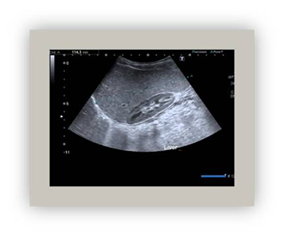

Ultrasound

This method is widely used and is based on sound waves, which means that it has no side effects. It is different from other imaging techniques because it allows to dynamic and real time visualization of anatomical structures (Figure 3).28,29

Figure 3 Abdominal US (The lien is seeing).